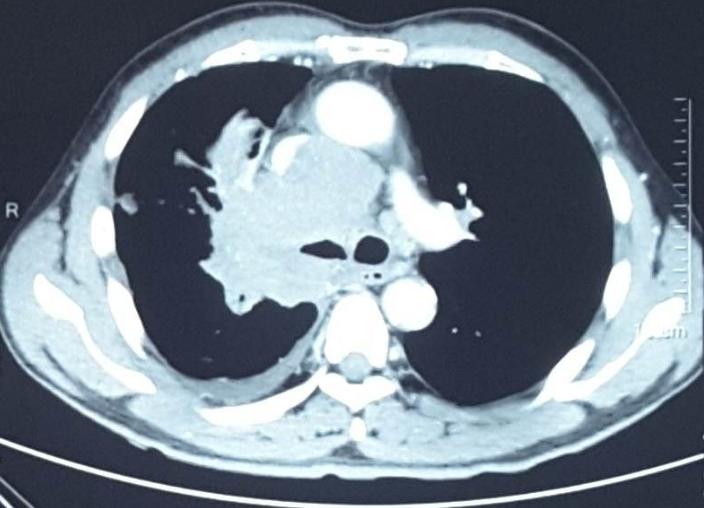

之前提到一部分肺癌患者是因为出现咳血这种症状后入院确诊为肺癌的,对于确诊肺癌已有出血症状的患者,我们科室是极为重视和谨慎的,一定要弄清楚出血原因。目前对于这部分患者,我们的临床经验是,出血最重要的原因为肿瘤包绕浸润血管导致血管破裂。(见下图),此类患者治疗过程中出血风险极高。对于此类患者,我们在治疗前会请介入科、呼吸科及气管镜室会诊,进行讨论,判断治疗过程中出血风险,甚至会治疗前对部分极易破裂的血管进行栓塞术,降低治疗过程中出现风险。